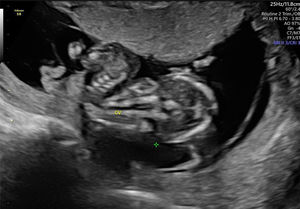

En la ecografía realizada al día siguiente en la consulta se objetivó un feto único en situación transversa izquierda con movimientos cardíacos fetales positivos. Se visualizó un encefalocele occipital de gran tamaño (fig. 1), con un defecto de la calota a nivel occipital y herniación importante de las estructuras cerebrales. En el extremo del encefalocele se objetivó una banda amniótica conectada al amnios (fig. 2). Asimismo, presentaba una ectopia cordis, con un importante defecto de la formación de la pared torácica anterior, ubicándose el corazón en el exterior de la caja torácica. En el estudio del corazón se visualizó que presentaba hipoplasia del ventrículo izquierdo. También se observó un gran defecto a nivel de la pared abdominal anterior, presentando gastrosquisis de gran cantidad de asas de intestino delgado y gran parte del hígado (fig. 3). Por último, a nivel de la columna se visualizó una cifoescoliosis severa a nivel lumbar (fig. 4). A nivel de placenta y anejos, la placenta se encontraba insertada en la cara anterior del útero con ecogenicidad acorde a la edad gestacional. En lo referente al amnios, este presentaba un fallo en la fusión con el corion (fig. 5). La cantidad de líquido amniótico era normal. No se encontraron otros hallazgos en la exploración ecográfica.